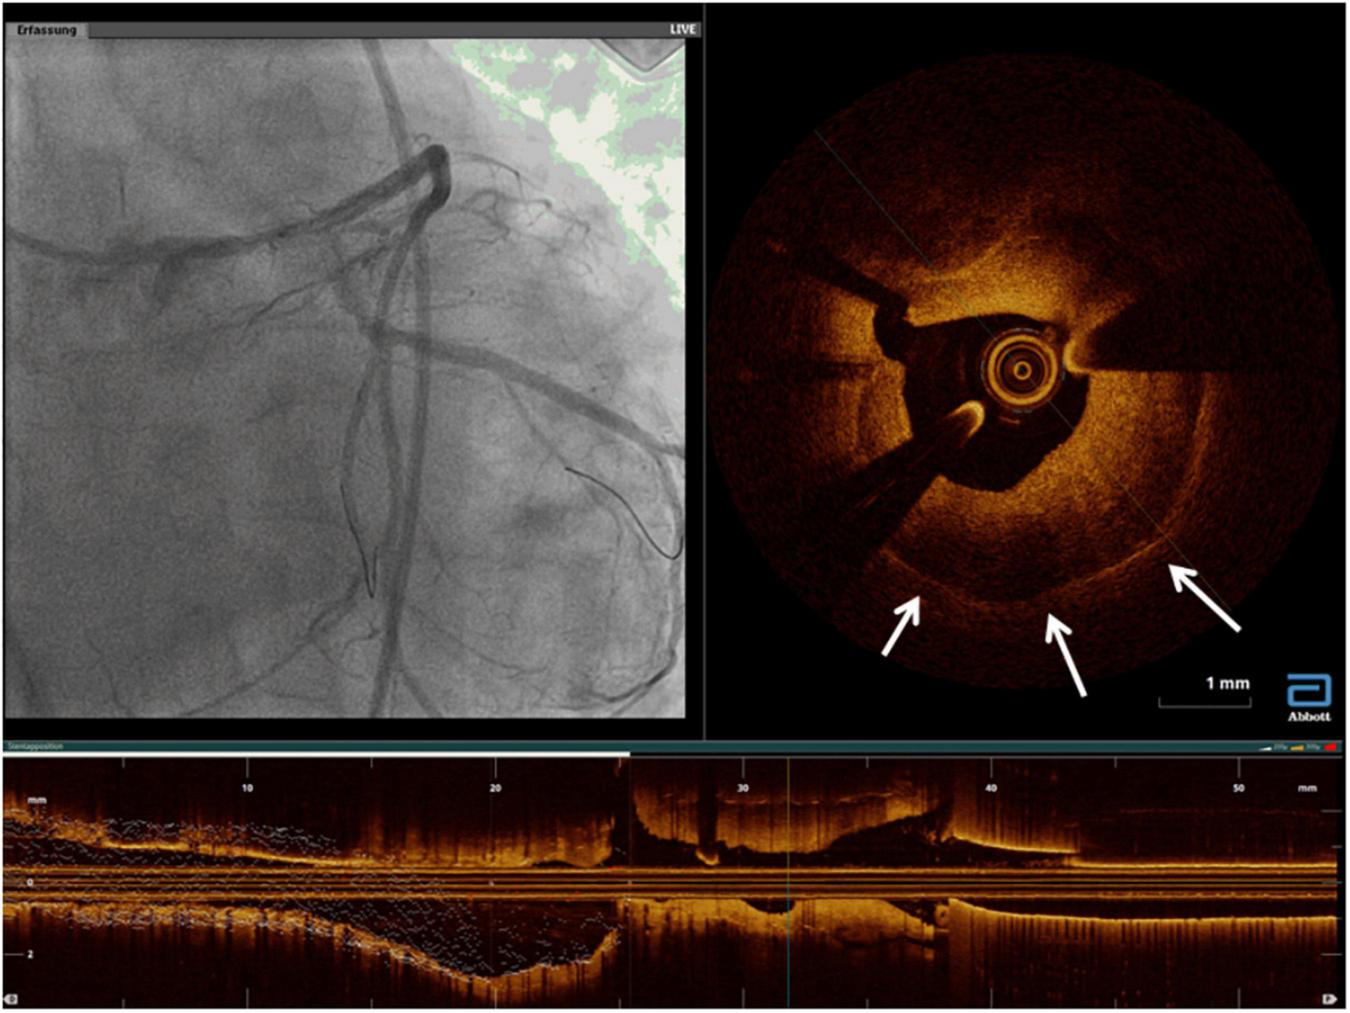

Because of a higher resolution, OCT has permitted more detailed characterization of the underlying etiology of ISR. Furthermore, it highlighted the morphologic difference between DES-ISR and BMS-ISR (117). In other words, OCT allowed better characterization of the neointimal tissue type, including identification of in-stent neoatherosclerosis, which could potentially guide therapy. In BMS-ISR, the typical pattern is a homogeneous high-signal tissue band, which is a characteristic of neointimal hyperplasia, with high smooth muscle cell content (Figure 11). In contrast, DES-ISR is typically characterized by attenuated, layered, heterogeneous tissue, which may represent proteoglycan-rich neointimal tissue, or neoatherosclerotic plaque (Figure 12) (118). Regions of the so-called peri-strut low-intensity (PSLIA) have been associated with accelerated restenosis due to inflammation, proteoglycan accumulation, and edema (Figure 13). Therefore, whereas neointimal formation peaks at about 6 months after BMS implantation, neointimal formation after DES implantation is a dynamic process that could creep out to even 5 years (118). In-stent neoatherosclerosis can also cause DES failure, through intimal rupture and thrombus formation, which usually presents with an ACS rather than stable angina (26). Of note, some studies suggest that stent age (i.e., longer implant duration) rather than stent type is the strongest and most consistent predictor of neoatherosclerosis (119).

FIGURE 11

Calcific neointima. The white arrows mark the stent struts, the left quadrant arc occupied by neointima presenting calcific neoatherosclerosis. The remaining homogeneous neointima is compatible with fibrous tissue.

FIGURE 13

A case of rapidly growing in-stent restenosis of the left main (3 months from previous angiography). The white arrows mark areas of peri-strut low-intensity compatible with inflammatory processes and with a rapid progression of disease.